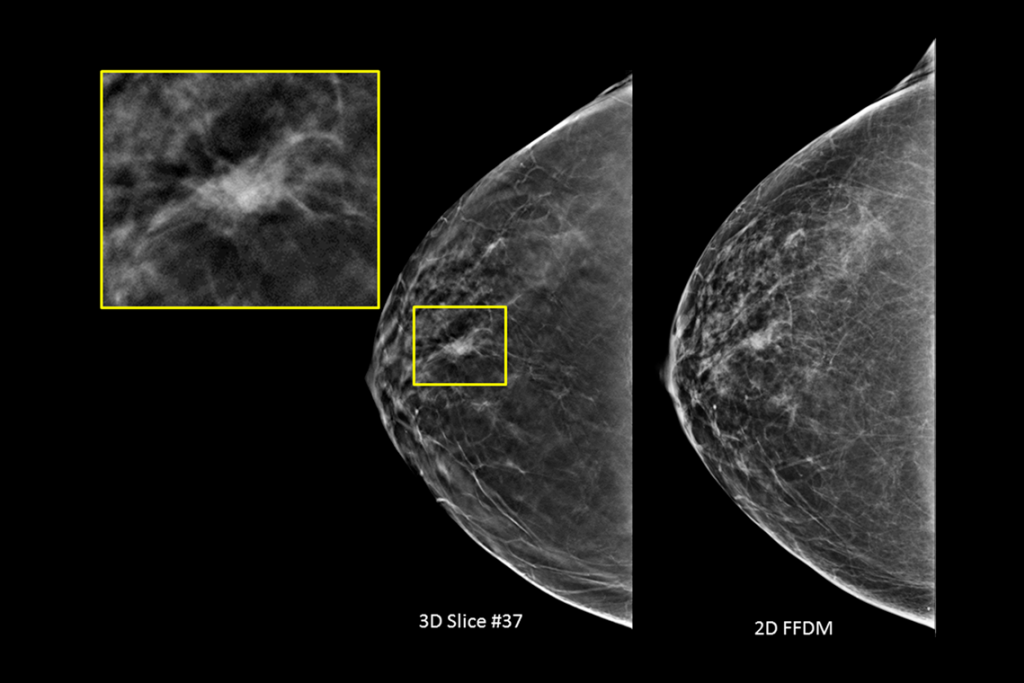

The 3Dimensions mammography system works with smart tomosynthesis technology, combining Clarity HD™ high resolution imaging, Intelligent 2D™ synthesised imaging and 3DQuorum™ SmartSlices for an efficient workflow.